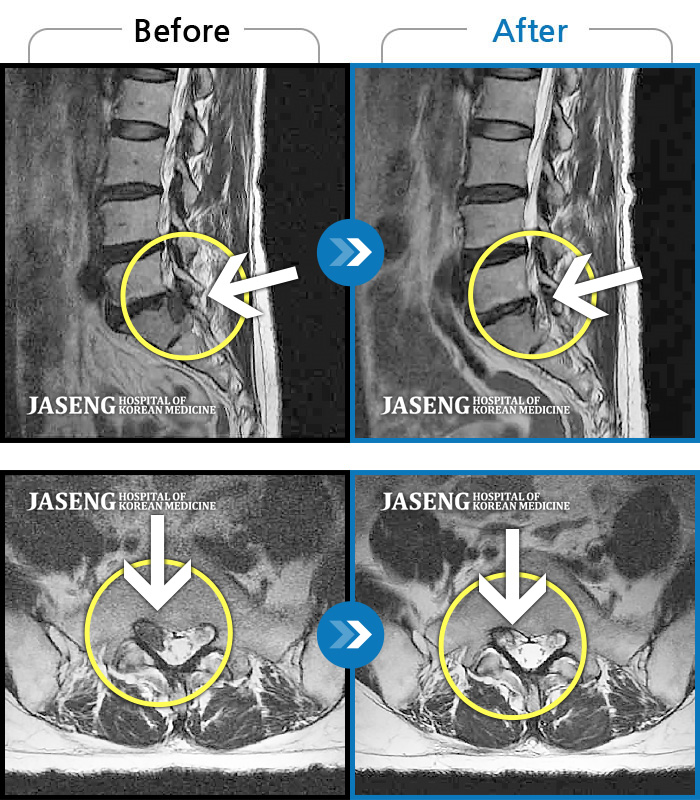

[뱸] 19.11.28~25.05.06

ȯںп Ǹ ǿ ԿǾ, ο ġ ۿ Ƿ ġḦ Ͻñ ٶϴ.